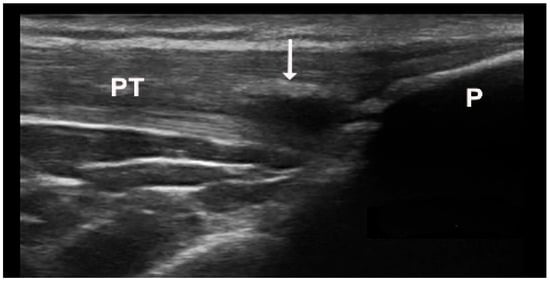

The double contour sign (DCS) indicates deposits of MSU crystals on cartilage surfaces, distinguishable from calcium pyrophosphate crystal deposits typically found within cartilage, highly specific for gout (Figure 2B and Figure 6A,B). Due to MSU crystal deposition, the reflectivity of the chondrosynovial interface is no longer angle-dependent, allowing for easy panoramic visualization of the entire chondrosynovial interface [18,19]. Like the tophus, the DCS should be sought in symptomatic joints, including the first metatarsophalangeal joints (dorsal and palmar planes) and the trochlear cartilage of the knees (suprapatellar plane in maximum flexion). The DCS may be less visible in thin cartilage (tarsal joints) or damaged cartilage, such as in osteoarthritis. Additionally, certain ultrasound features can be mistaken for a DCS, leading to false positives due to several factors: first, the normal hyperechoic appearance of the synovium, where the hyperechoic band appears regular, like a line drawn with a pen. A “true” DCS adheres to the cartilage during dynamic movements. Second, the presence of joint effusion enhances the echo of the posterior wall (increased ultrasound propagation) and may accentuate the normal hyperechoic appearance of the synovium. Finally, thin cartilage (small joints and/or associated osteoarthritis) with chondrocalcinosis and calcium deposits often localized in the intermediate layer of the cartilage [14,16]. Regarding the diagnostic performance of the DCS sign, a recent study by Cipolletta et al. emphasized that dynamic examination significantly improves the effectiveness of US in differentiating between gout and calcium pyrophosphate dihydrate CPPD crystal arthritis. Their results indicated that, with dynamic examination, the DCS sign moved with the cartilage in all cases of gout, whereas it moved in the opposite direction in CPPD patients. [20]. In 2022, Filippou et al. conducted an anatomical cadaver study to compare US DCS findings with pathological features, aiming to evaluate how crystal location affects ultrasound characteristics. The study was performed on upper limb joints until calcium pyrophosphate (CCP) deposits were detected according to OMERACT criteria. The affected joints were then examined pathologically, with crystal deposition described. The findings concluded that monosodium urate (MSU) crystals in gout are located directly on the chondral surface and cause the DCS sign to move with the cartilage. In contrast, CCP crystals are found in capsules and/or ligaments, above the hyaline cartilage, and do not exhibit dynamic sliding during US examination [21].

Figure 6.

Ultrasound features of “double contour sign” visible on the cartilage surface of the femur (A) and first metatarsal bone (B).